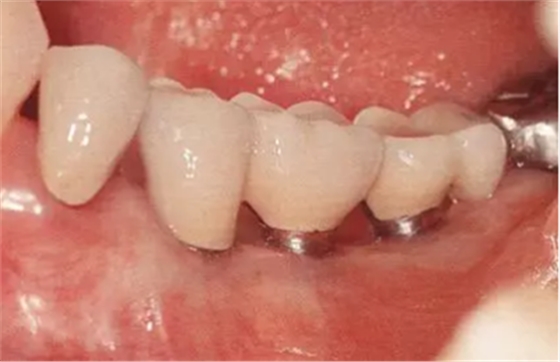

▲圖10-3,4

圖10-3 第二次手術前的(牙合)面照。

圖10-4 為了在頰側、舌側進行FGG,在上頜腭側采集大塊移植片

▲圖10-5,6

圖10-5 第二次手術后的舌側面照。遠中側進行APF,近中側進行FGG。

圖10-6 頰側也進行FGG,縫合后確認移植片不會移動。